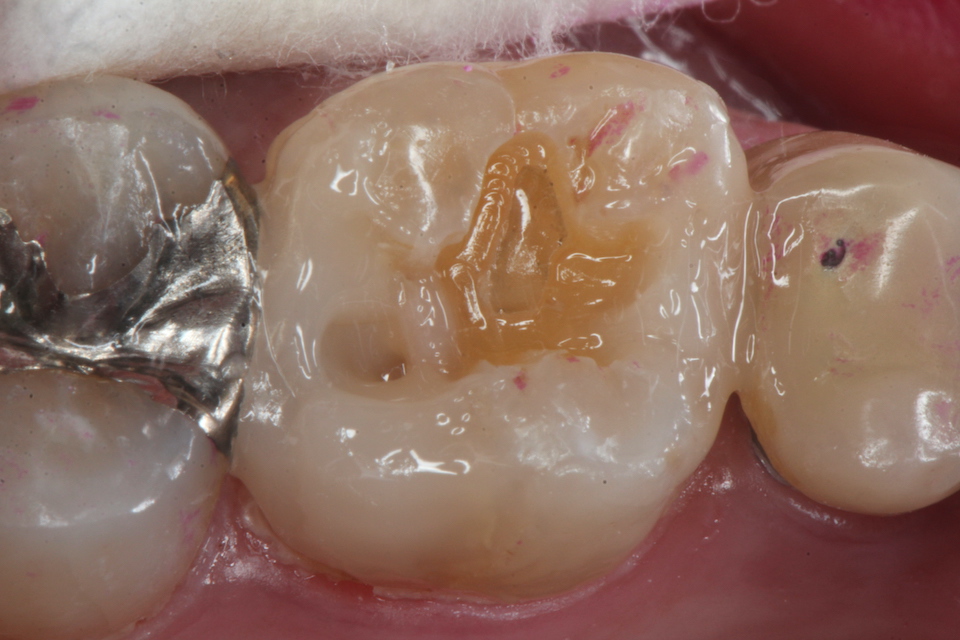

残根上のCR(ダイレクトボンディング)8 2025.11.12

ブリッジ脱離で2次カリエス+Perでグラグ… 2025.11.01

ブリッジ脱離で2次カリエス+Perでグラグ… 2025.10.31